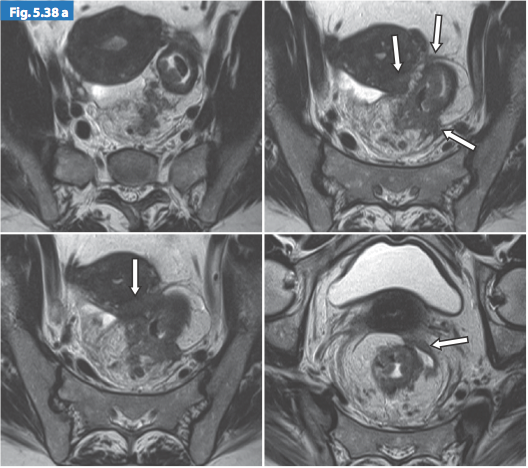

- T4: được chia T4a: khối u trực tiếp xâm lấn thanh mạc hoặc cân mạc treo trực tràng. T4b: khối u xâm lấn trực tiếp hoặc dính vào các tạng, cơ quan khác.

Hình 6. Sự giảm tín hiệu của khối u xâm lấn vào thành sau âm đạo

Hình 7. Khối u giai đoạn T4 trên hình ảnh T2w axial xâm lấn lá phúc mạc và cổ tử cung

Hình 8. Khối u giai đoạn T4 trên hình ảnh T2w sagittal xâm lấn âm đạo

và cân mạc treo trực tràng